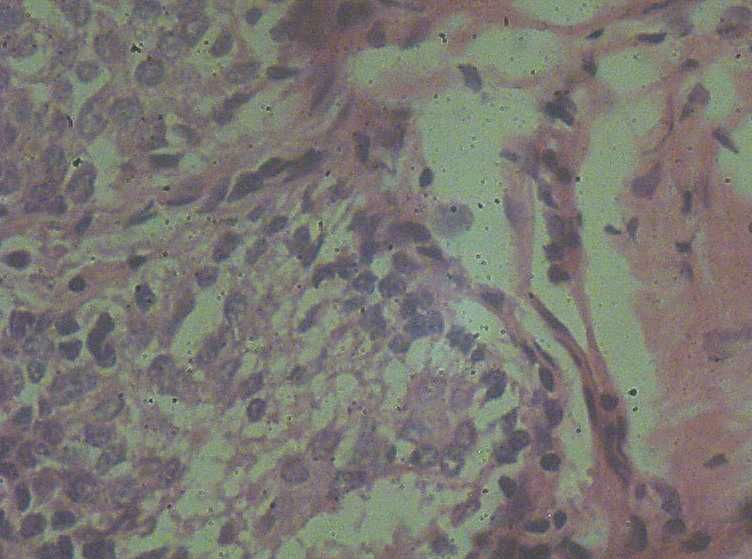

女41岁,左腺包块。肉眼:不整形囊壁样组织,大小2*1.6*0.3CM,壁厚0.1—0.3,未触及结节,未见出血及坏死。

标签:乳腺纤维囊性增生症

这例报了 慢性囊性乳腺病。不知可否?